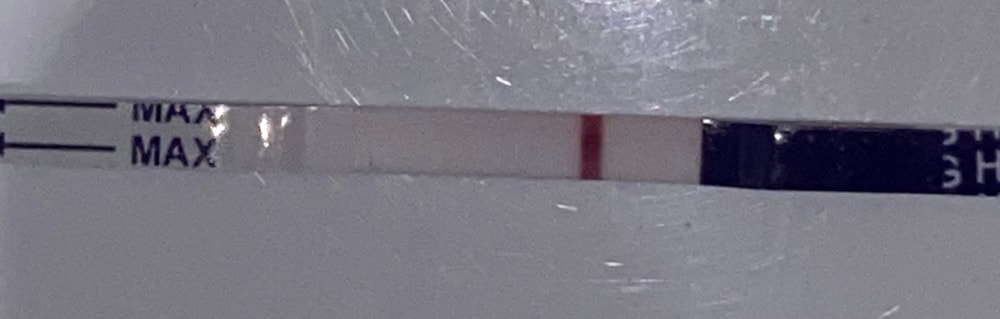

Вчера клиаблю непонятно что мне нарисовал, поэтому сегодня я снова сделала тест))

фоткала под разными освещениями. Очень уж хочется, чтобы кто-то кроме меня тоже увидел полоску🤣🤣 фотки, где теста два - верхний это вчерашний утренний, а нижний сегодняшний. Видите ли вы что-нибудь?🥺

На нижнем вижу //

Я вижу, цепляет глаз. У меня 7-8 дпо, сама начала тесты делать, хотя понимаю рано. Но разглядываю и надеюсь